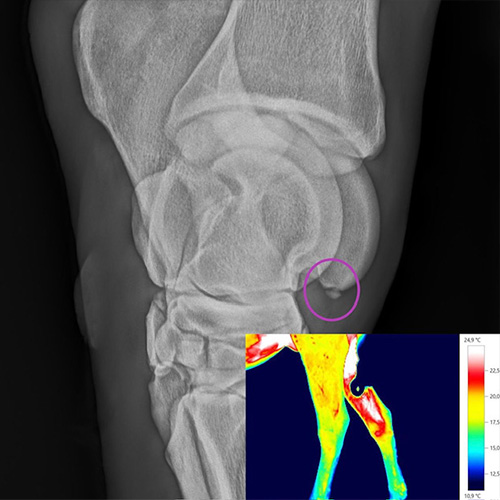

Durch das digitale Röntgensystem der Firma Oehm und Rehbein ist es möglich, die röntgenologische Untersuchung am Patienten, direkt im Stall durchzuführen und auszuwerten.

Die hochauflösende Detektorplatte überträgt die durch die Röntgenstrahlung entstandenen Daten innerhalb von 5 Sekunden auf den Computerbildschirm. Die Röntgenbilder werden in der Praxis archiviert und können per E-Mail dem Besitzer und Kollegen zur Verfügung gestellt werden.